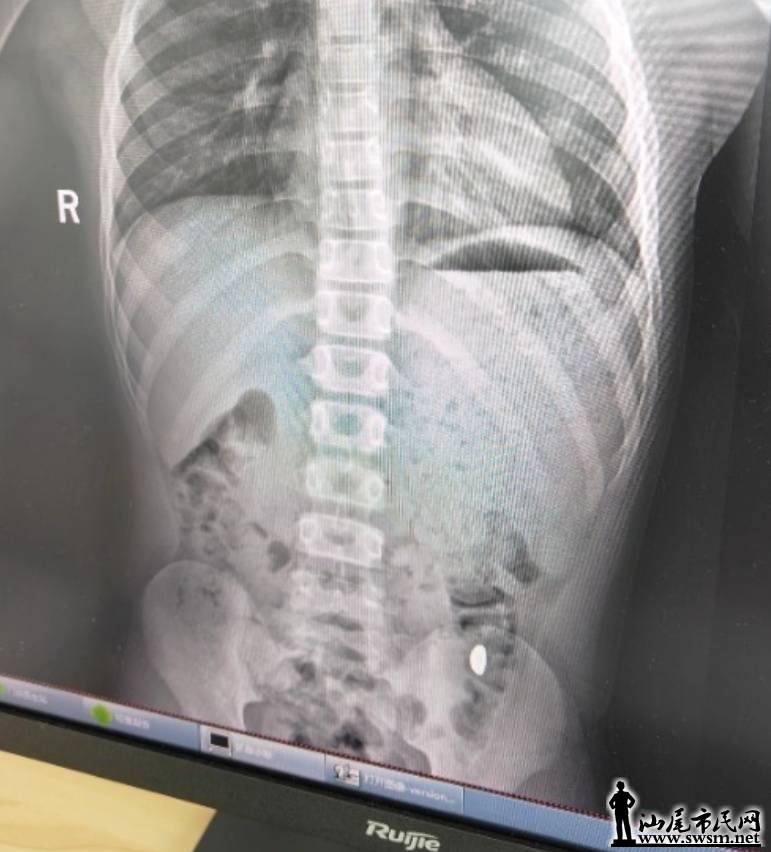

右下加亮点为金豆。